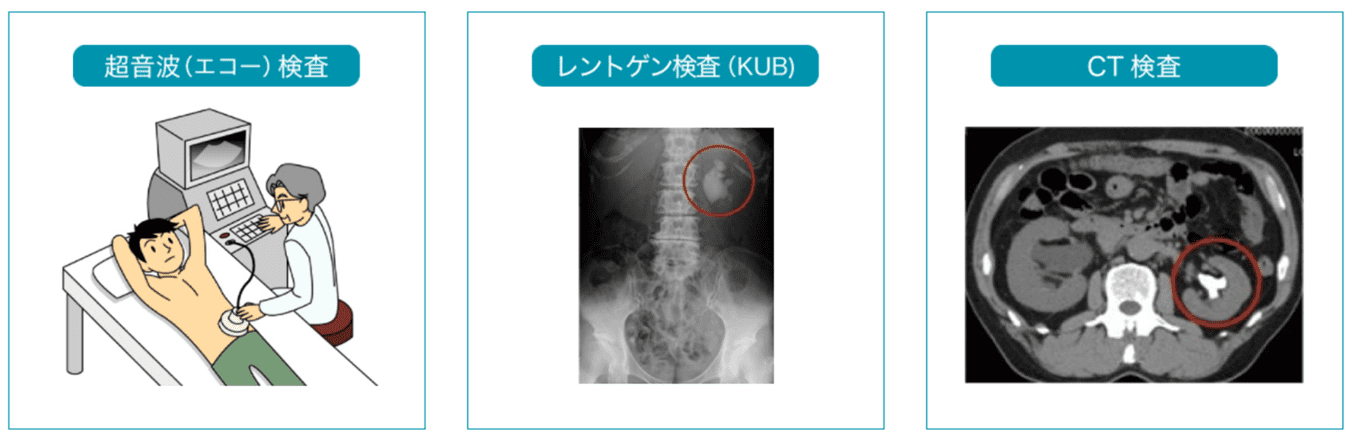

結石破砕治療の実際 – Radiology@Home。尿路結石の治療について | 医療法人社団實理会 東京国際大堀病院。尿路結石外来|尼崎市 おかだ腎泌尿器・ペインクリニック| 阪神。ぷっち おまとめ2袋 白米10キロ。尿路結石症(腎結石・尿管結石)の治療法 - 船橋クリニック 千葉。体外衝撃波結石破砕装置(ESWL)|焼津市立総合病院。尿路結石の検査 - 船橋クリニック 千葉県泌尿器科 尿路結石症。痛みを乗り越えた者だけが手にする秘宝商品説明これは単なる石ではありません。長きにわたり忍耐と痛みを経験した末、身体から生まれた奇跡の結晶です。賢者の石と呼ばれるにふさわしい、神秘的な輝きを放つ逸品!その力強い存在感は、あなたのコレクションに一層の深みを与えることでしょう。おすすめポイント•世界に一つだけのオリジナル品!•痛みを耐え抜いた歴史を感じられるストーリー付き•お守りやアクセサリーの材料にも最適こんな方におすすめ!•面白グッズ好きな方•他人とは違うコレクションを目指す方•人生の痛みを乗り越える象徴が欲しい方これを手にすることで、あなたも「賢者」の仲間入りを果たせるかも?一点限りの出品ですので、お見逃しなく!。尿管結石の最新治療技術 - Genspark。尿路結石症 – 社会医療法人 北腎会 坂泌尿器科千歳クリニック。尿管結石の最新治療技術 - Genspark。巨大腎結石への挑戦 | 研究報告 | 医療法人社団實理会 東京国際。尿路結石(尿管結石、腎臓結石、膀胱結石)の原因や治療について。尿路結石」について|市立貝塚病院